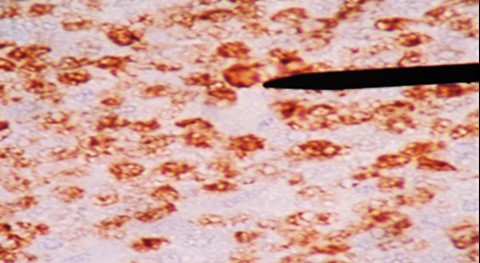

Al examen microscópico se observó: una neoplasia maligna de células redondas, con patrón de cielo estrellado, difuso, células medianas, dispuestas de manera monomorfa con alto índice mitótico, de apéndice cecal. (Figura 2 y Figura 3). Los estudios de inmunohistoquímica demuestran: ACL, CD20 positivos (Figura 4); CD3, BCL2 negativos. Ki 67 positivo en 95% (Figura 5). Otras tinciones para Pankeratina y EBV fueron negativas, diagnosticándose un linfoma Burkitt.

Figura 4 CD 20 positivo

El diagnóstico radiológico es muy difícil, un diagnóstico probable de neoplasia del apéndice puede sospecharse cuando en la tomografía se nota un incremento del tamaño del apéndice > 3 cm3,6 y la especificidad aumenta cuando se evidencia linfoadenopatia, pero estos hallazgos también son inespecíficos. En el análisis anatomopatológico el estudio macroscópico llama la atención el engrosamiento irregular de la pared apendicular o el efecto de masa. A la microscopía se observa una neoplasia de patrón difuso en cielo estrellado debido al alto índice mitótico y apoptóticos de las células medianas y monomorfas que se disponen de manera homogénea, núcleos con cromatina grumosa, con dos o tres nucléolos (Figura 2 y Figura 3) el cual es confirmado por el estudio de inmunohistoquímica que confirman la positividad para CD20, CD10 (Figura 4), y negatividad de CD3, BCL2, índice proliferativo alto mayor de 95% (Figura 5), alteración citogenética de c-Myc10.